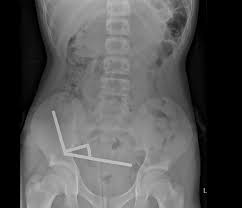

After four days of abdominal pain, the teenager sought medical help. Scans revealed that the magnets had formed four separate chains inside his digestive tract, forcefully clamping sections of his bowel and large intestine together. The resulting pressure caused necrosis—the death of intestinal tissue due to restricted blood flow—and posed a severe risk of perforation and infection.